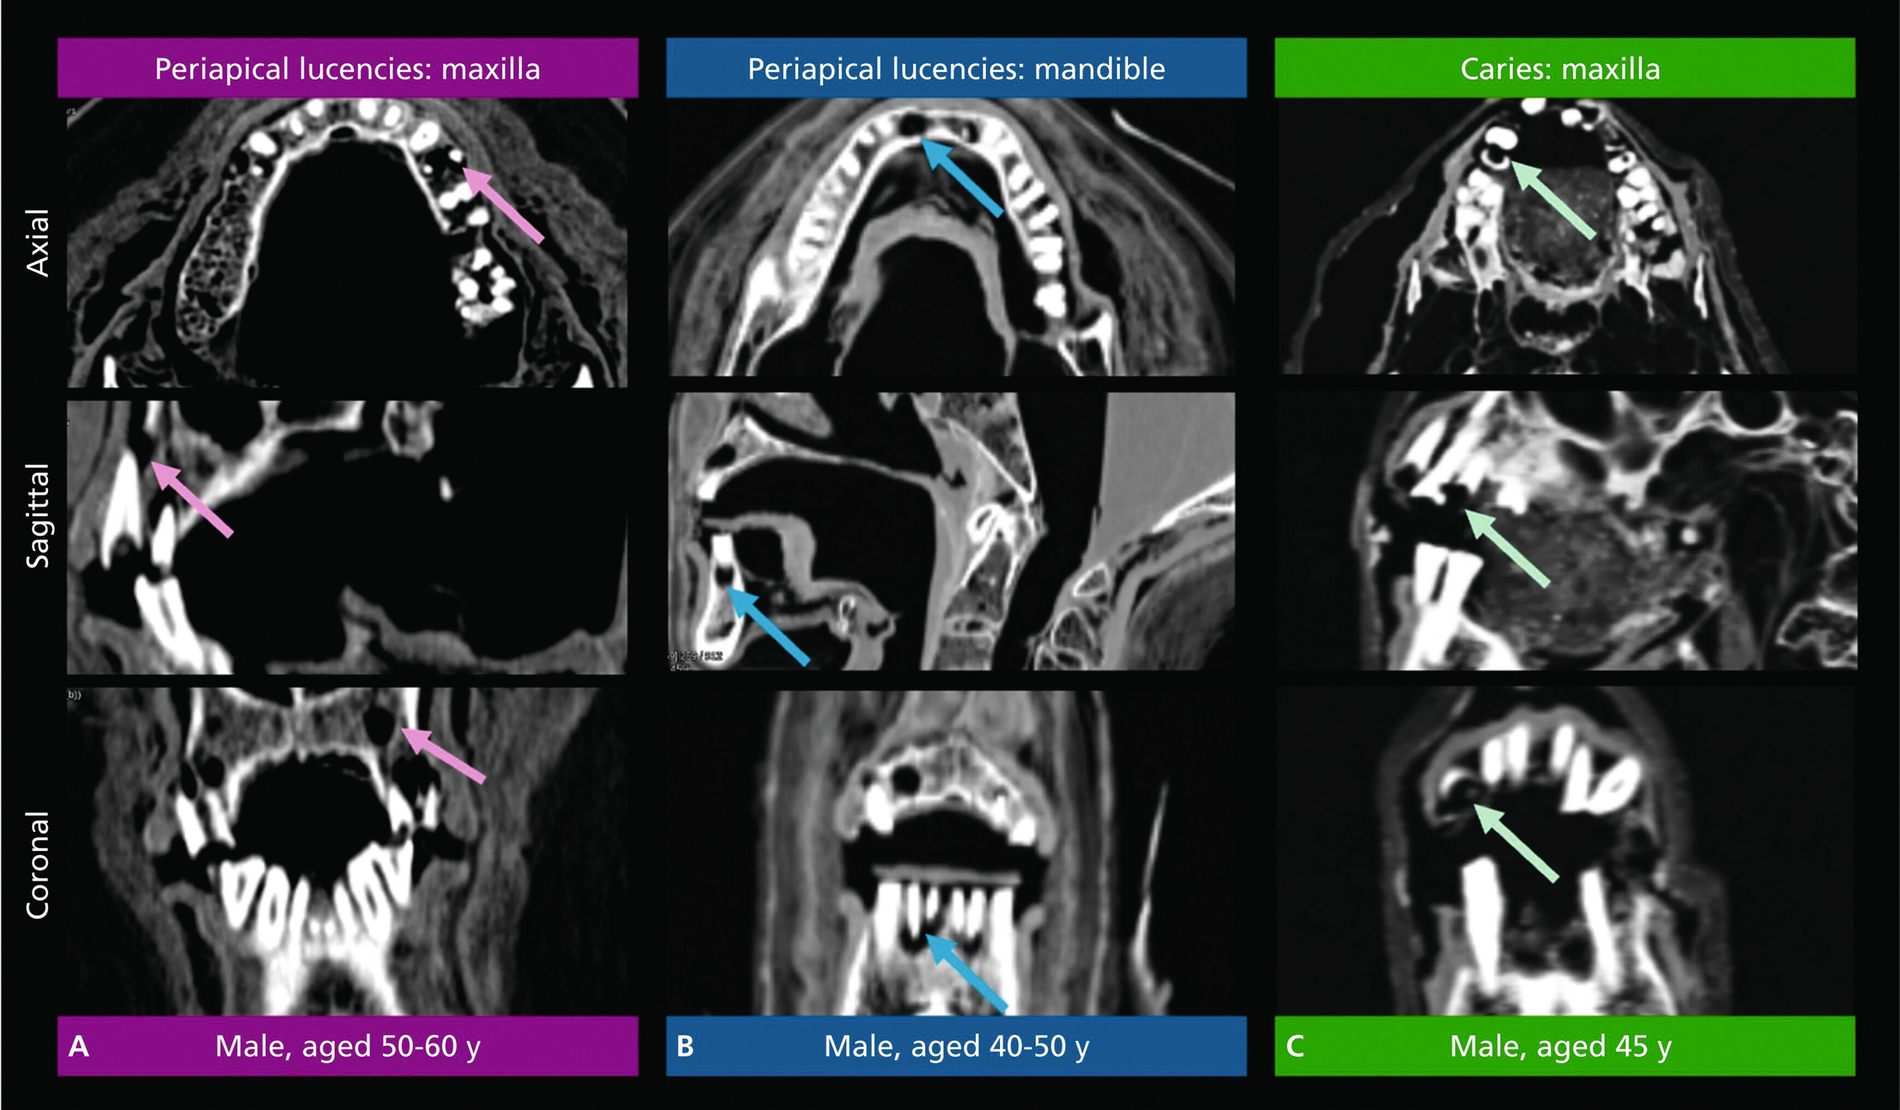

Zu den Zähnen mit Karies zählten sowohl solche, die vermutlich aufgrund von Karies abgebrochen waren, als auch solche, die nach dem Bruch Karies entwickelten. Bei intakten Zähnen wurde das Vorhandensein von Karies anhand unregelmäßiger Aufhellungen im Schmelz und im Dentin festgestellt. Aufgrund des verwendeten Bildgebungsverfahrens war die Erkennung von beginnender und früher Karies jedoch unwahrscheinlich.

Periapikale Aufhellungen wurden als gut abgegrenzte Aufhellungen an den Wurzelspitzen mit oder ohne offensichtlichen Knochenverlust definiert. Schließlich wurde die Messung des Abstands zwischen Schmelz-Zement-Grenze (cement-enamel junction, CEJ) und Alveolarkamm (alveolar crest, AC) als maximal messbarer Wert pro Zahn verwendet, da Ablagerungen und postmortale Veränderungen mehrere Messungen pro Zahn erschwerten.